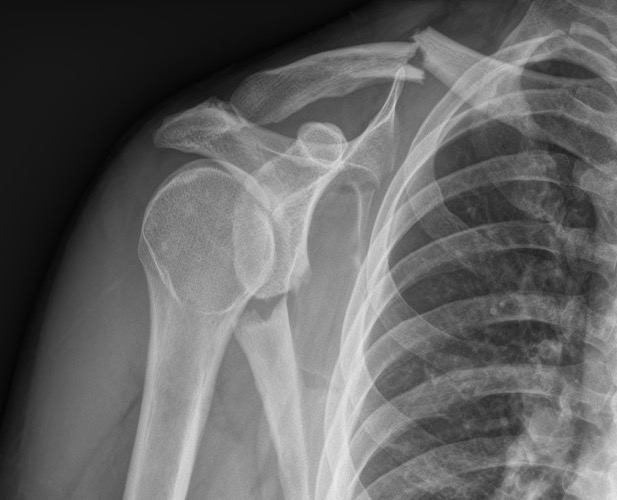

Floating shoulder

Combined scapula body fracture / intra-articular glenoid fracture